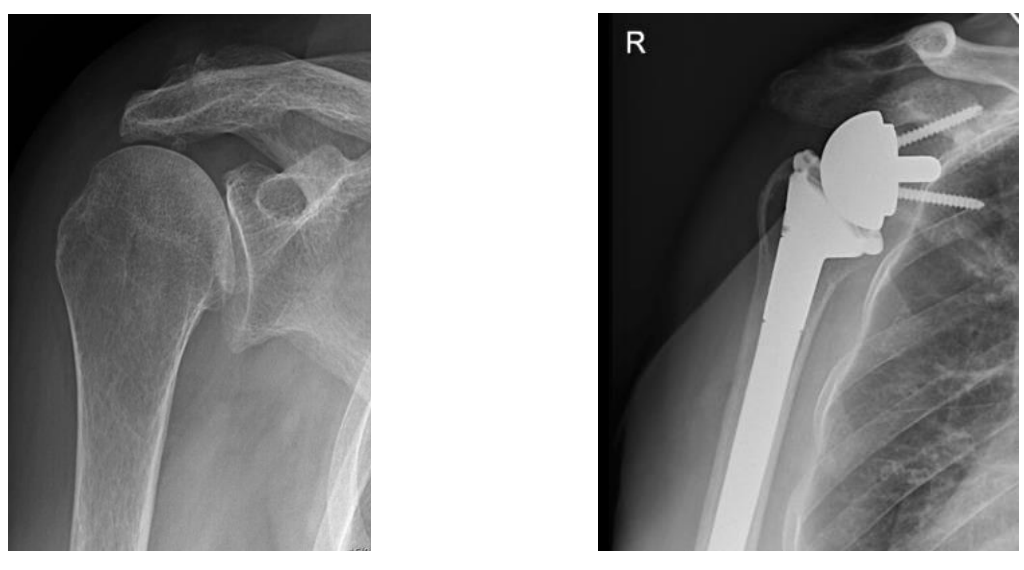

Fractuur prothese (C)

Prothese dewelke gebruikt wordt bij breuken van de schouderkop.

Omgekeerde schouderprothese (D)

In geval van ernstige slijtage in combinatie met een afgescheurde schouderpees, bij onherstelbare invaliderende scheur van de schouderpees of in geval van complexe breuken bij patiënten met slechte bot- en peeskwaliteit.